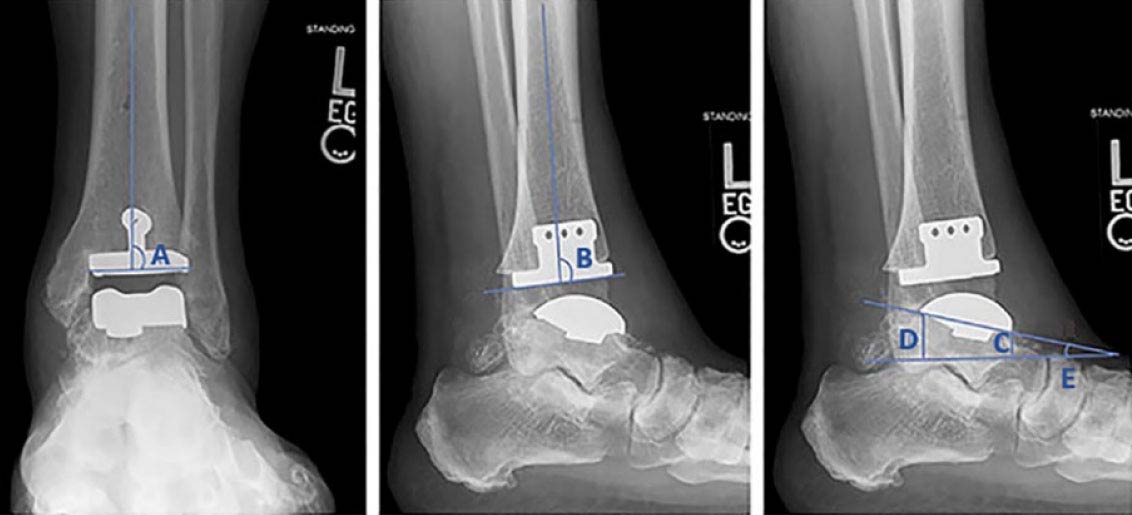

In this longer-term follow-up of a limited cohort (48 patients/50 ankles, average age at index surgery: 64 years), Salto Talaris fixed-bearing total ankle arthroplasty demonstrated good long-term survival (Kaplan-Meier estimated survivorship was 84.2%) with relatively low rates of revision or other complications. Patient-reported outcome and range of motion measures revealed good stability.

Source: Veale M, Endo A, Veale N, et al. Salto Talaris fixed-bearing total ankle arthroplasty: long-term results at a mean of 10.7 years. Foot Ankle Orthop. 2024;9(1):24730114231225458. doi: 10.1177/24730114231225458.